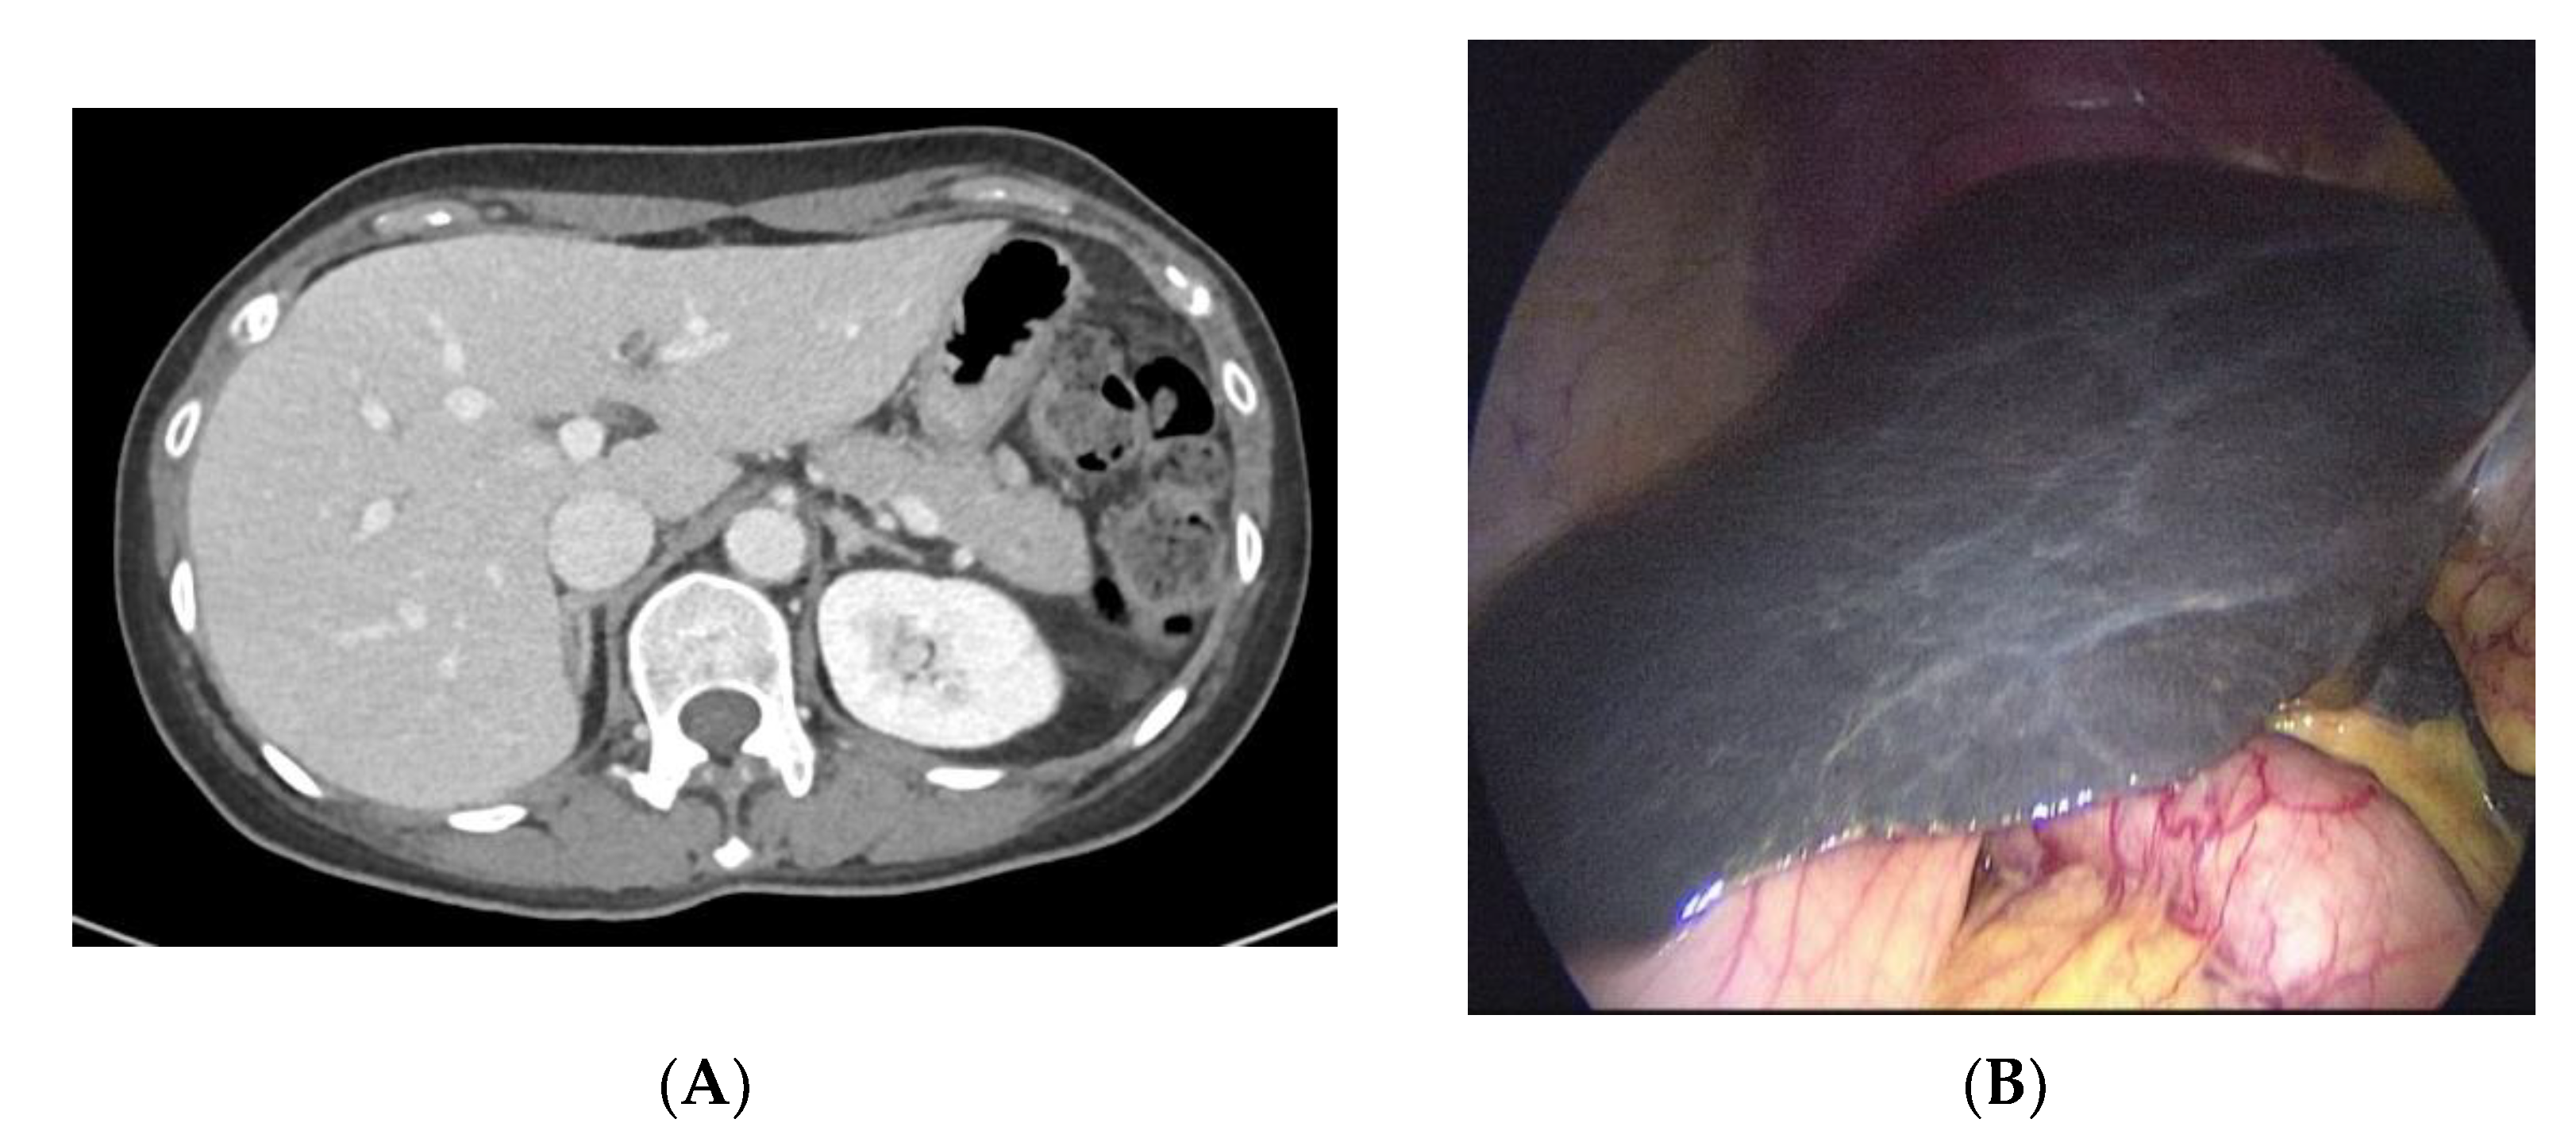

2. Case Report